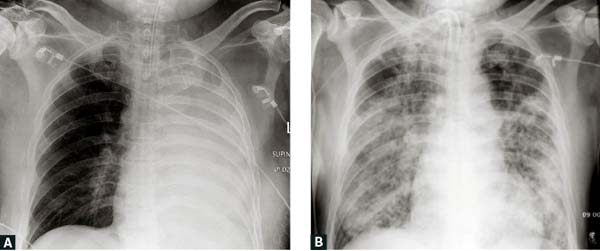

Hình 2.

A.  !important;Phim chụp X-quang ngực từ một người đàn ông thổ dân châu Úc (Aboriginal), 54 tuổi, mắc tiểu đường type 2 kiểm soát kém

cho thấy tổn thương đông đặc phổi trái hoàn toàn và đòi hòi phải được đặt ống nội khí quản khi được khám;

B.  !important;Phim chụp X-quang theo dõi điều trị của người này trong bệnh viện vào ngày 28,

cho thấy melioidosis phổi cấp tính tiến triển có các thâm nhiễm phế nang hai bên lan rộng.

Các đặc điểm lâm sàng của melioidosis bắt chước nhiều căn bệnh khác (vd nhiễm trùng máu/sốc nhiễm trùng, viêm phổi mắc từ cộng đồng [CAP] và lao phổi,điều này khiến các bác sĩ thường xuyên chẩn đoán sai căn bệnh này.5  !important;Vì vậy, melioidosis được biết như là ‘kẻ bắt chước vĩ đại’.1 Thời gian ủ bệnh trung bình là chín ngày (1–21 ngày) nhưng các triệu chứng có thể xuất hiện nhanh hơn (<24 giờ) sau khi hít phải và/hoặc sặc nước nhiễm bệnh.1,9 Trong các ca bệnh cấp tính, nhiễm trùng máu là hội chứng phổ biến;>50% các bệnh nhân có vi khuẩn trong máu khi được khám, và 20% phát triển thành sốc nhiễm trùng.5 Ở người lớn thì nhiễm trùng phổi là thể nhiễm trùng cấp tính phổ biến nhất (Hình 2), gây ra >50% những người được khám, trong khi viêm phổi được ghi nhận ở xấp xỉ 20% các ca trẻ em.8 Các ca trẻ em bị nhiễm trùng da thường xuyên hơn (60%) so với các ca người lớn (13%).5,10 Melioidosis ở da thường biểu hiện với một tổn thương riêng lẻ tại vị trí xâm nhiễm, thường không đáp ứng với các loại kháng sinh tiêu chuẩn.5,6 Các áp-xe nội tạng thường được ghi nhận phổ biến ở lá lách, gan, tuyến thượng thận và thận,5 và, chủ yếu ở Úc, các áp-xe tuyến tiền liệt xảy ra ở xấp xỉ 18% nam giới (Hình 3).

Nhiễm trùng phổi  | Biểu hiện ở 51% người lớn (Hình 2) !important; biểu hiện ở 20%trẻ em5,8  |

Các biểu hiện X-quang có thể thay đổi: các thâm nhiễm nhỏ/tổn thương tạo hốc (cavitation)/bệnh phổi mô kẽ8  |